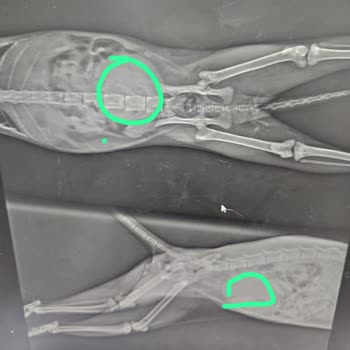

148

Kendimi bu yorumu yapmak için ancak toparlayabildim çünkü bu klinikte M*** bey ve ekibi, canımızın evimizin her şeyi Şaşkın'ımızın ölümüne sebep oldular. Her şeyi tarihleri ve kanıtları ile buraya yazacağım. 6 Şubat günü Şaşkın gece çok halsizleşti, idrar yapamıyordu ve bir kere kusmuştu. 7 Şubat gü...